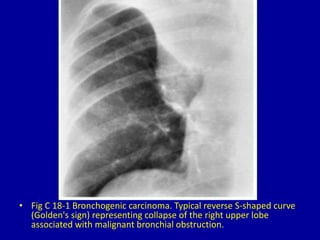

• Fig C 18-1 Bronchogenic carcinoma. Typical reverse S-shaped curve

(Golden's sign) representing collapse of the right upper lobe

associated with malignant bronchial obstruction.

• Fig C18-1 Bronchogenic carcinoma. Typical reverse S-shaped curve (Golden's sign) representing collapse of the right upper lobe associated with malignant bronchial obstruction.